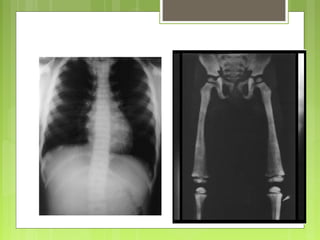

A nivel de la cadera: las localizaciones más frecuentes son próximas a los

cartílagos de crecimiento